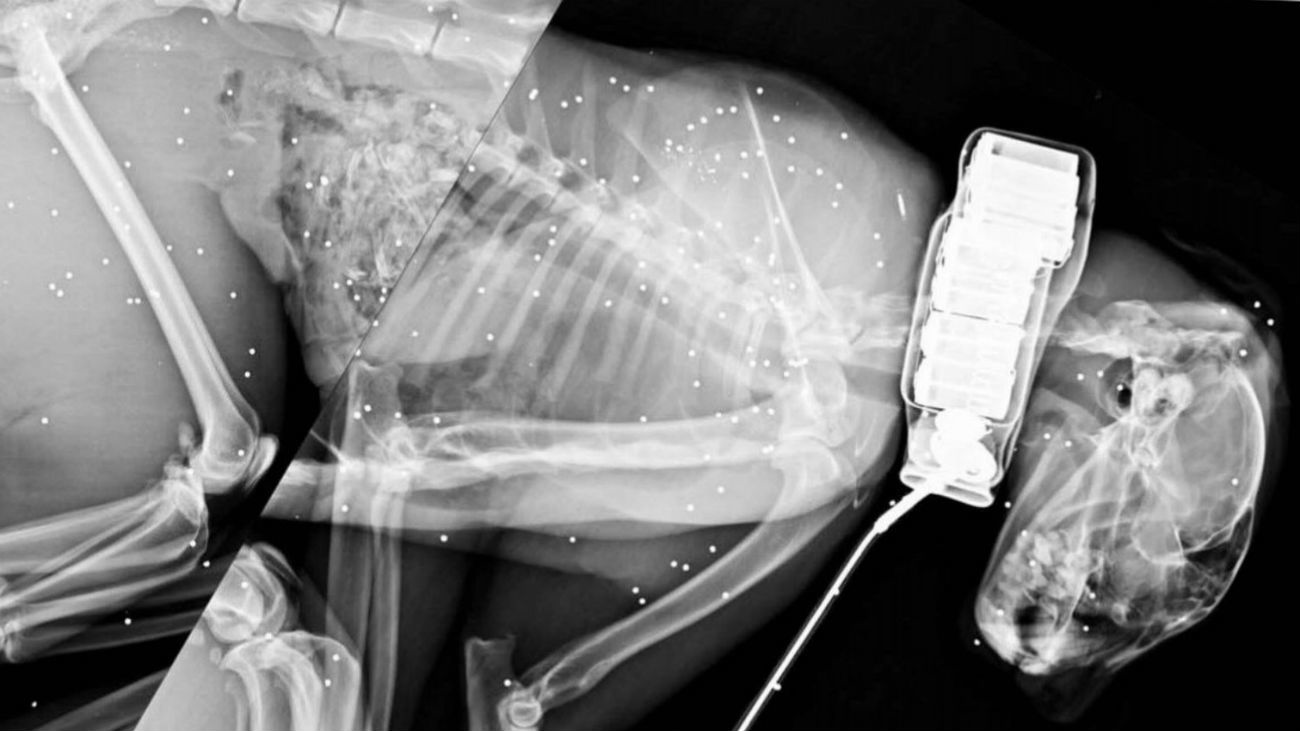

50 linces ibéricos han muerto a mano de los cazadores furtivos. Más de 150 han sido atropellados en las carreteras de toda España. Todo ello, esquilma a una especie que se encuentra en peligro de extinción.